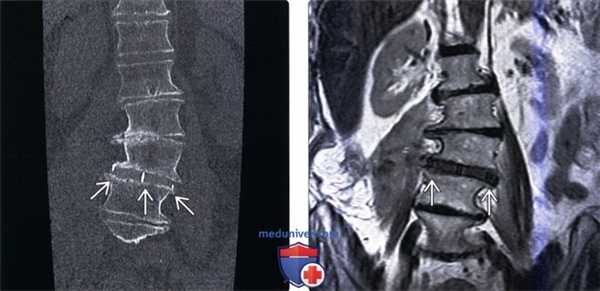

(Слева) КТ, фронтальный срез: дискогенный склероз замыкатель -ных пластинок L2-L3 слева и L3-L4 справа S3. Асимметричная дегенерация связана с перераспределением нагрузки у данного пациентов со сколиозом. Феномен вакуума виден в области нескольких межпозвонковых дисков.

(Справа) КТ, фронтальный срез: признаки тяжелого многоуровневого дегенеративного поражения межпозвонковых дисков с потерей высоты межтелового пространства, эбурнеацией кости и феноменом вакуума на уровнях L5-S1, L3-L4 и L2-L3. Обратите внимание на выраженный дискогенный склероз на уровне L5-S1 и левосторонний дегенеративный сколиоз.

(Слева) Т1-ВИ, фронтальная проекция: признаки умеренно выраженного левостороннего сколиоза с вершиной на уровне L3-L4. Имеет место правосторонний боковой листез L1 и L2 позвонков, потеря высоты межтеловых пространств и дегенеративные изменения замыкательных пластинок.

(Справа) Т2-ВИ, фронтальная проекия: признаки жировой инфильтрации костного мозга в смежных с дегенеративно измененными дисками участках. Обратите внимание на диффузные изменения замыкательных пластинок позвонков и боковой листез, связанный с тяжелой дегенерацией диска.